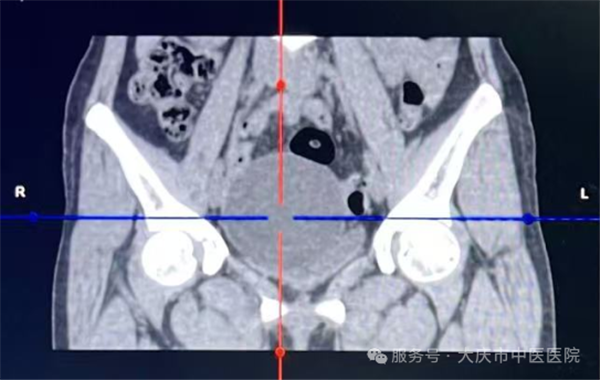

对于体积较大(如直径超5cm)的良性卵巢囊肿,若出现压迫症状或存在潜在风险,经医生综合评估后,可考虑采用这种微创方式。该技术无需腹部切口,仅通过细针操作,就能在精准定位下完成病灶处理,大幅降低对身体的损伤。

这项技术的核心优势在于“精准微创”,手术全程在超声实时监控下开展,医生通过细针经皮肤穿刺进入囊肿内部,先将囊液彻底抽出,再向囊内注入硬化剂,破坏囊肿内壁的分泌细胞,有助于降低复发风险。整个操作无需切开腹部,创伤仅为针尖大小,对周围组织影响极小。

从临床操作来看,这类手术流程规范,医护团队会严格执行无菌操作,全程监控穿刺路径与针尖位置,确保每一步操作精准可控。由于创伤极小,患者术中多无明显腹部不适感,出血量极少,整台手术耗时通常不足30分钟,能最大程度减少对正常生活工作的干扰。